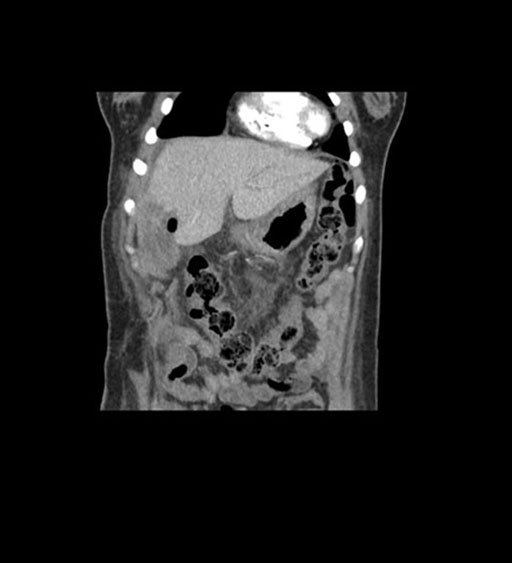

Axial Arterial

Axial Venous

Coronal Arterial

Coronal Venous

Imaging analysis

Based on initial findings, which issue(s) would you be most concerned about?